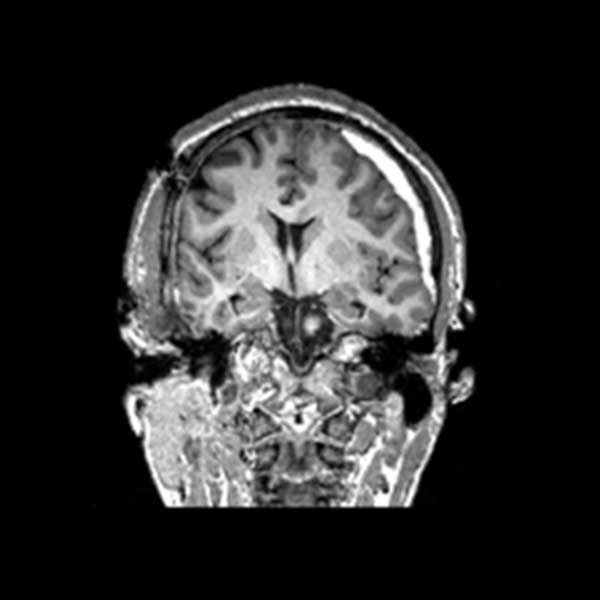

In the two scans below, the bright white areas towards the right of the scans show a hemorrhage, shifting the brain across its midline to the other side.

Images by TRACK-TBI